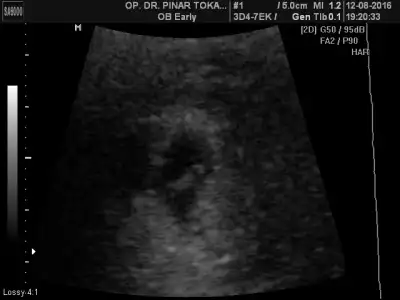

7. Hafta karından ultrason görüntüsü. 27 mayıs 2016 son adet tarihi. Eşimin doğum tarihi 12 aralık 1980, benim doğum tarihim 1 eylül 1983...

Tahminin nedir canım?